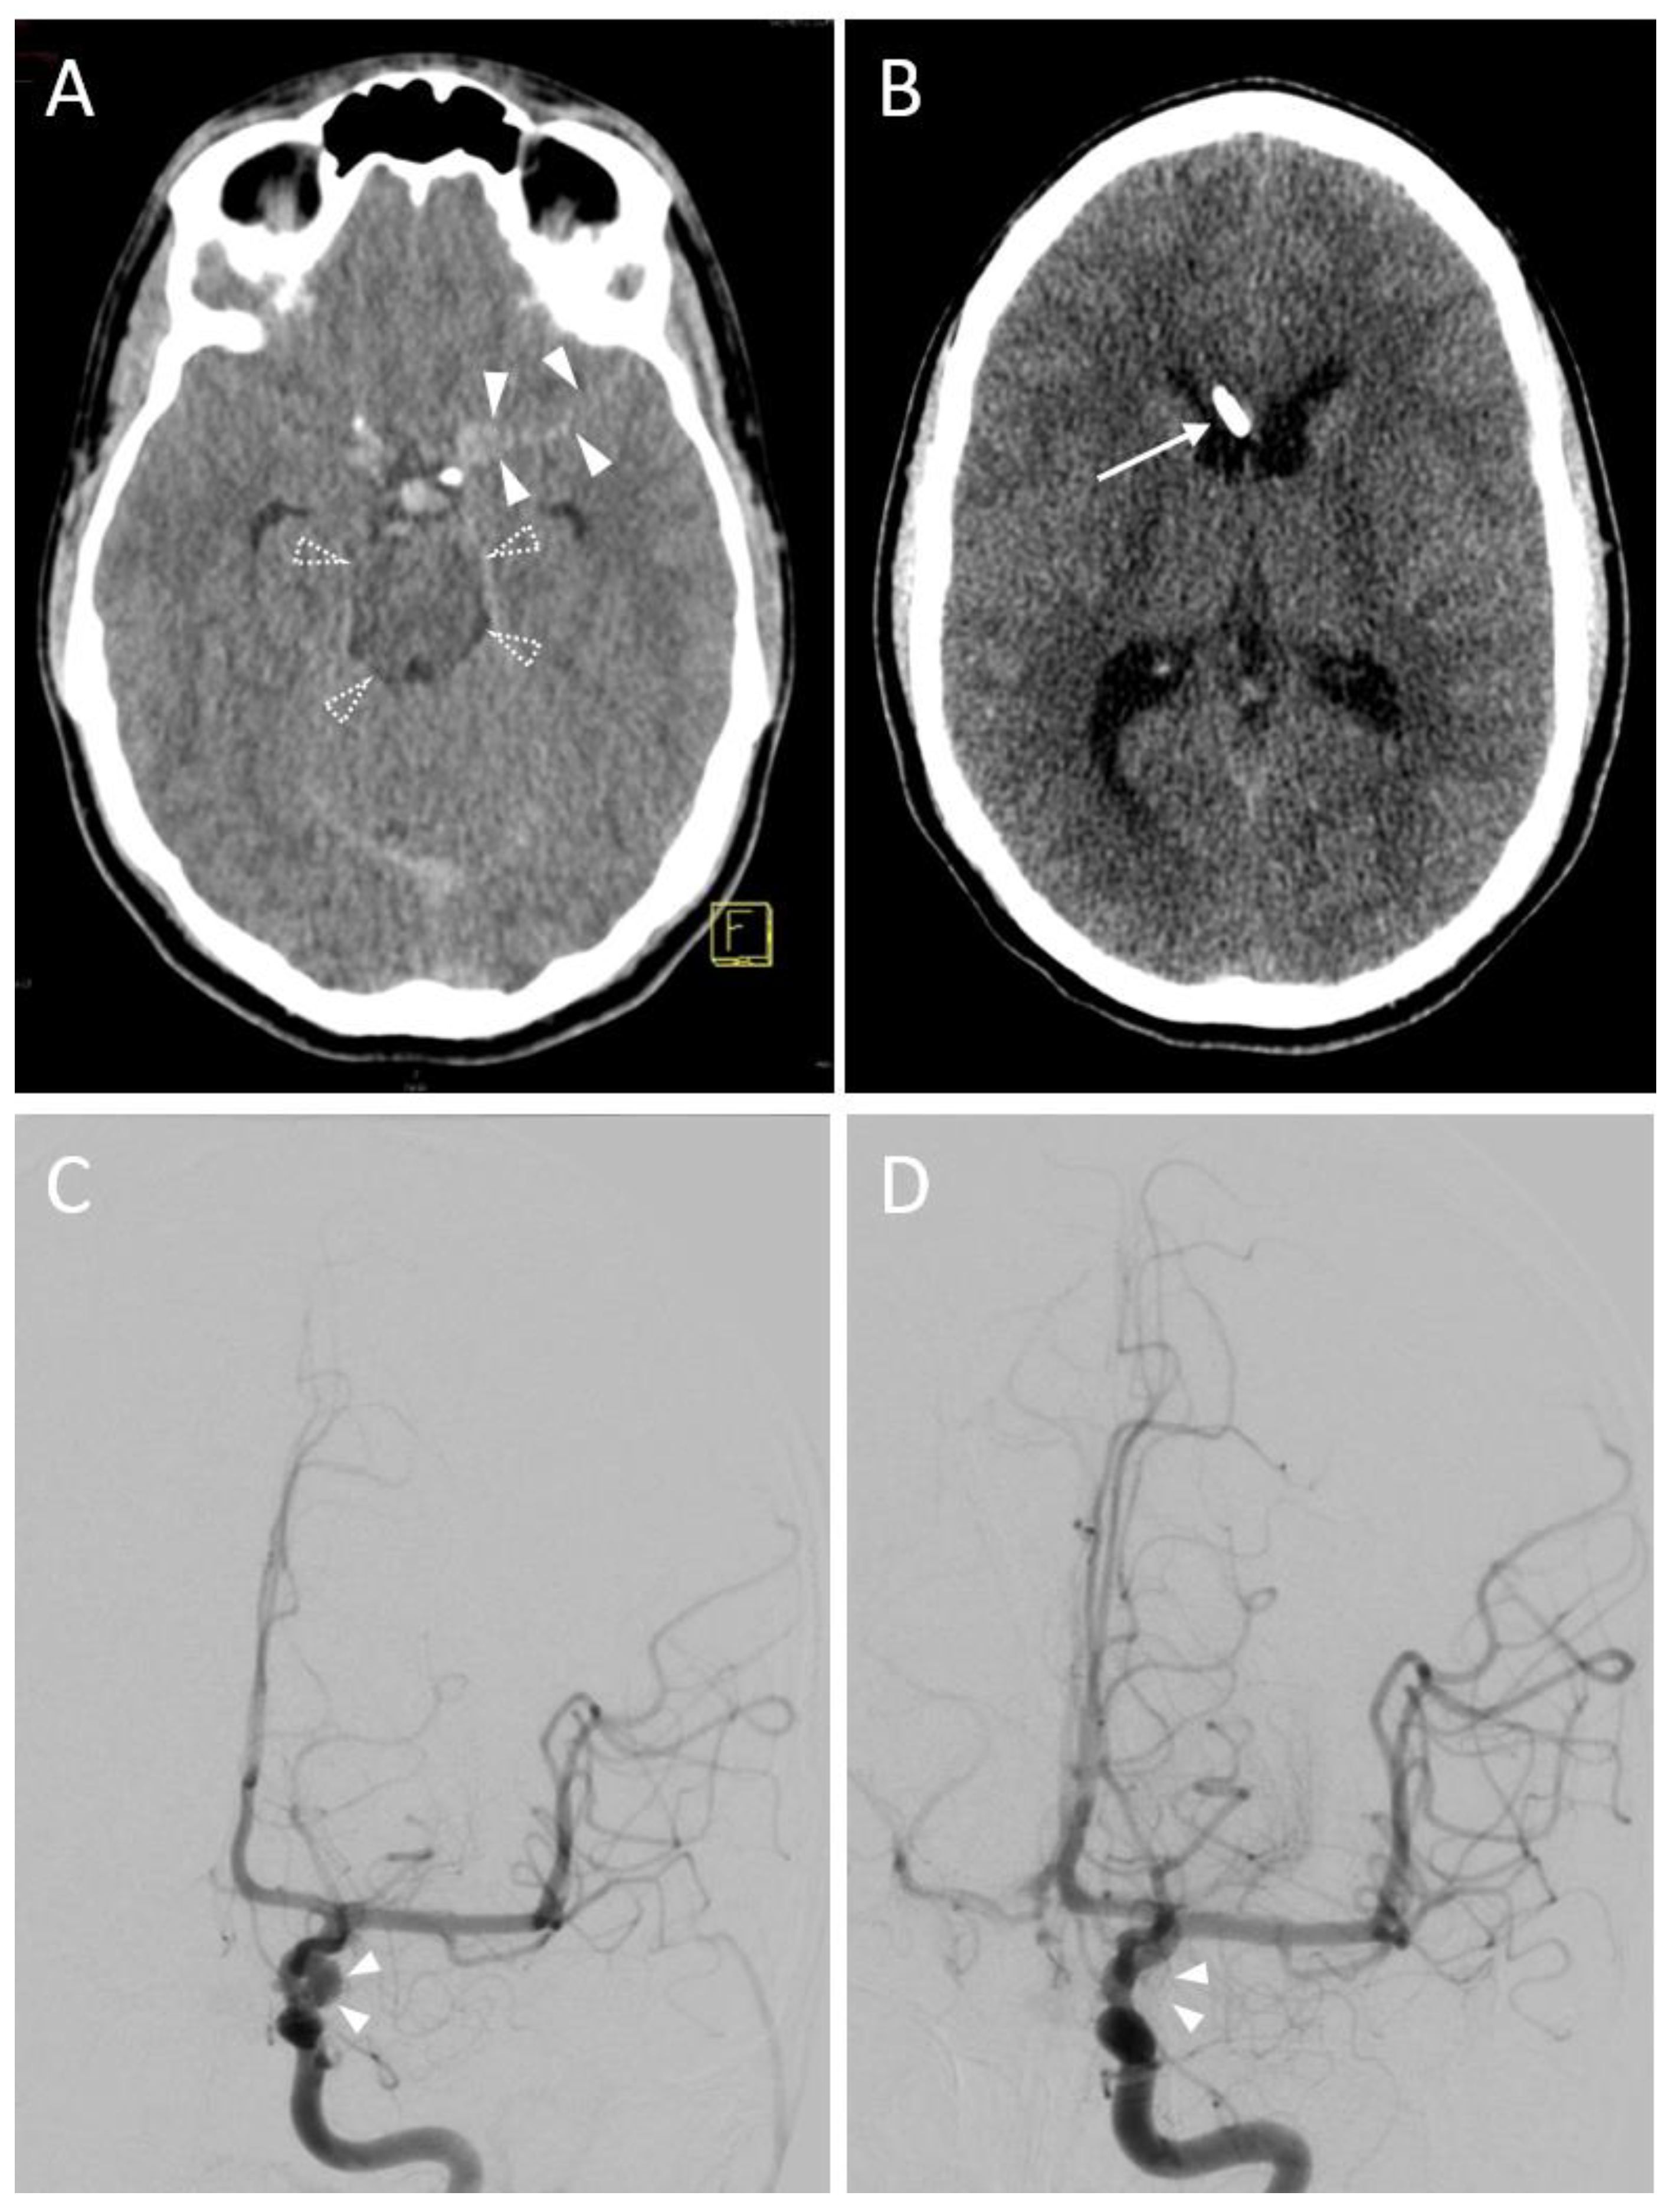

3.2.4. Hemorrhage

| ICH 4 (non-traumatic) | 7 (24.1) 2 |

| Arteriovenous Malformation | 3 (10.3) 2 |

| Aneurysm | 1 (3.4) 2 |

| Hemorrhage on follow-up CT | |

| No evidence of hemorrhage | 32 (88.9) * |

| Grade 1 (<1 mL) | 3 (8.3) * |

| Grade 2 (≥1 to 15 mL) | 1 (2.8) * |

| Grade 3 (>15 mL) | 0 (0.0) * |